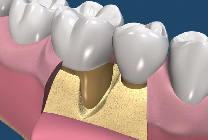

牙周再生手術是一種要求較高的牙周手術,其成功取決於多種條件的滿足,這些條件是:嚴格的適應證選擇;牙齦的炎症被有效控制;骨內袋中的肉芽組織應當儘可能被清除;生物膜在齦溝“領口”處應與牙根面盡量密合,以保證無齦上皮長入;生物膜與牙根之間應保持充分的空間,即足夠的膜根間隙;齦瓣應將生物膜完全覆蓋;術前術後有效的菌斑控制。(圖07-11)

圖7